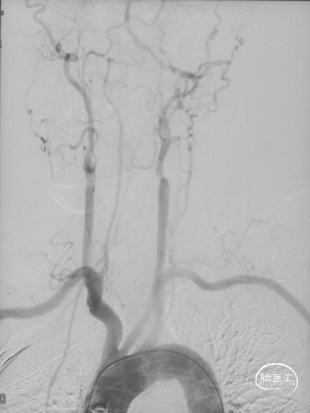

CTA和DSA

CTA和DSA所见:双侧颈内动脉闭塞,右侧椎动脉发出PICA后闭塞,左侧椎动脉V1-V2段闭塞。两条健壮的侧枝通过肌支吻合汇入左椎动脉V2段,构成了整个大脑大部分供血的主要来源。双侧颈外动脉亦有少量血流供应颅内。这样的颅内供血很容易发生失代偿,导致TIA甚至脑梗。